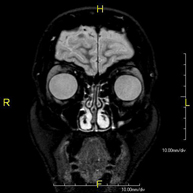

- Orbit MRI

This non-invasive diagnostic procedure uses an electromagnetic field and radio waves (from a transmitter and receiver) to acquire high-definition anatomical images of the orbits. It is a radiation-free procedure. Indicated for: double vision, trauma, suspected tumour, hyperthyroidism.